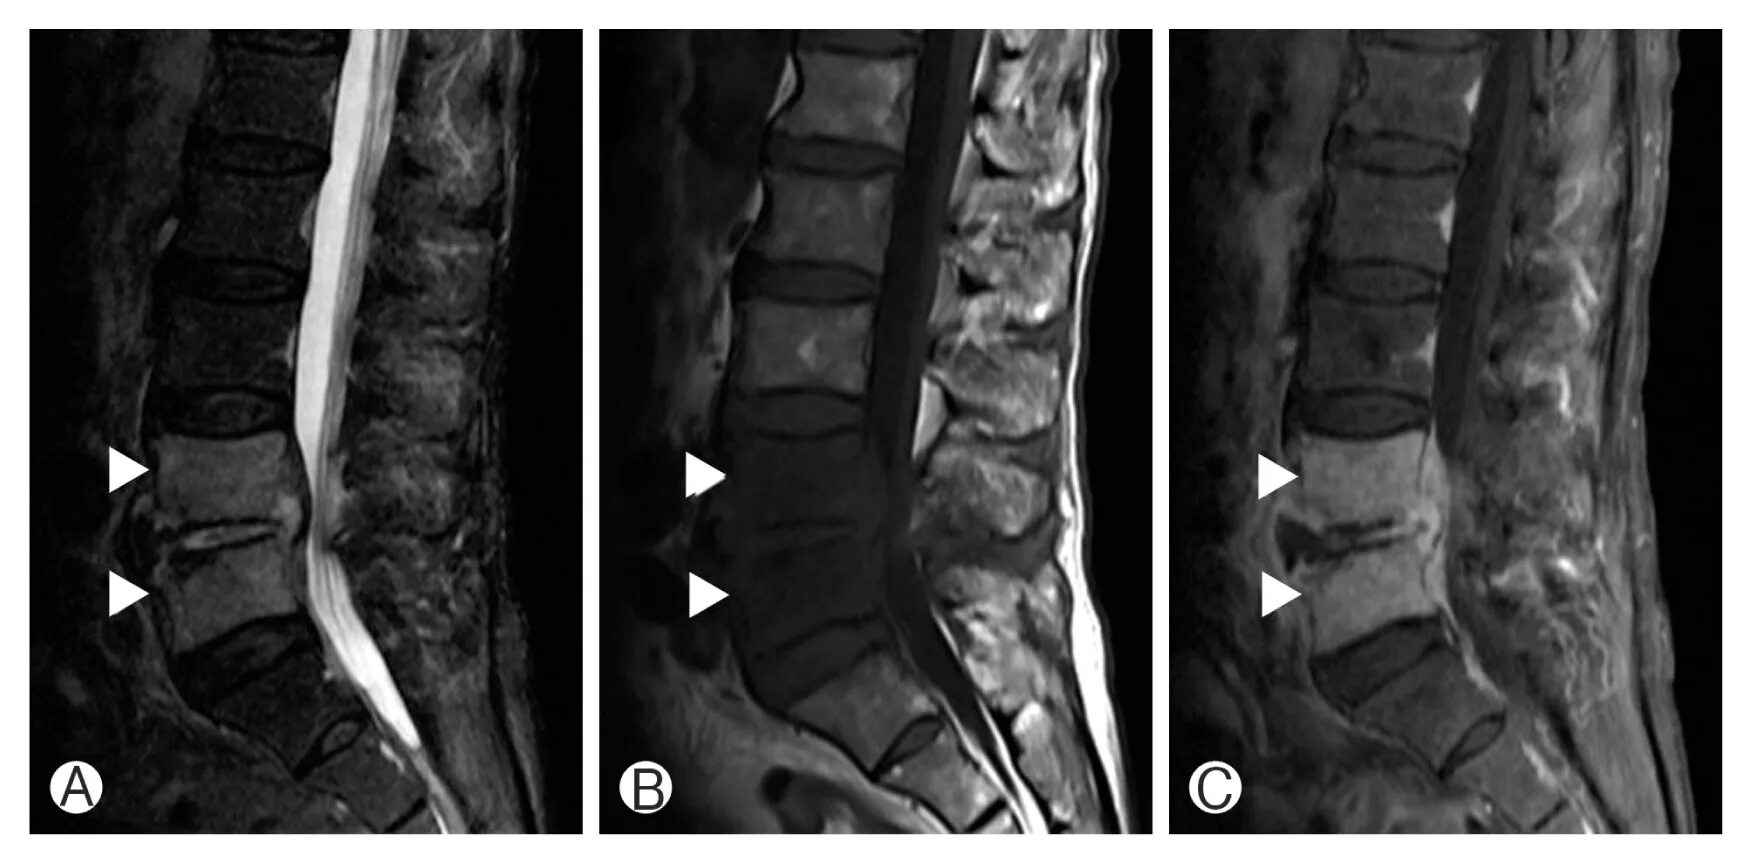

Перед мрт позвоночника можно кушать